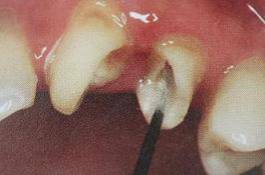

必要的情况下先开阔根管口建立一定的视角后,慢速手机上G钻为引导钻,由号递增引导开阔通路;P钻预备桩道,同样需要由小向大号递增,直到选择好适合的号预备到规定测量的深度即可,再配合纤维桩系统中各型号纤维桩所匹配的桩道钻,预备、修整成与纤维桩相适应的桩道。

预备后根管壁上会不同程度的牙胶和封闭剂等残留物,所以桩道预备前后建议X线片辅助检查预备深度等情况,而残留物也会很清晰地显现。